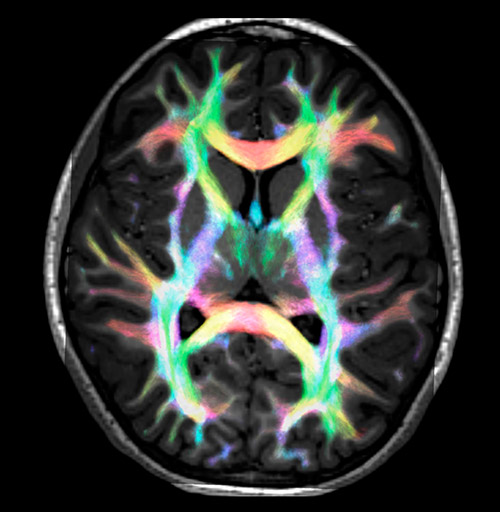

Crossing fibers of the corpus callosum bordered by the superior longitudinal fasciculus as well as within in the pons.

Fiber tracking from the left and right hippocampi to the fornix.

Fiber tracking from the left and right hippocampi to the fornix (green), and the corticospinal track based on a seed region of the posterior limb of the internal capsule.

Super-resolution directionally encoded color track-density imaging overlaid on T1-weighted structural MRI.

All images were created from the same acquisition in a child using Ingenia 3.0T CX and 32-channel dS Head coil. Diffusion data was acquired at b-values 0, 500, 1000, 2000, 3000. The use of high b-values (3000 s/mm2) effectively suppresses extra-axonal water signal and provides high angular resolution.

Data processing was performed using open source software. Fiber tracking was performed using the MRtrix package (J-D Tournier, Brain Research Institute, Melbourne, Australia, https://github.com/MRtrix3/mrtrix3), Tournier et al. 2012. DEC TDI based on F Calamante et al 2010.